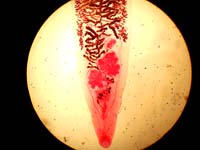

Bệnh nhân là một nữ 21 tuổi Afghani woman, gần đây có đến Đức, phàn nàn về một số triệi chứng trên cơ thể là nổi mày đay cấp tính. Xét nghiệm ký sinh trùng học 4 mẫu phân thu thập trong 2 tuần cho thấy có trứng Dicrocoelium dendriticum và amíp thể không gây bệnh. Điều trị prednicarbate và praziquantel (3 × 600mg trong 3 ngày) được đề nghị. Do tình trạng cô ta là người tị nạn, nên bệnh nhân không được theo dõi. Sán trưởng thành D. dendriticum sống trong túi mật và đường mật của vật chủ. Trứng sán thải qua cùng phân, sau đó nó đựợc nuốt vào bởi ốc sống trên cát .ốc thải ra cercaria trong chất nhầy của ốc, chất nhầy này sau đó bị kiến ăn. Kiếm nhiễm ấu trùng dính vào ngọn cỏ, động vật ăn cỏ sẽ ăn chúng có kèm theo kiến nhiễm.Trên các động vật này, sán trưởng thành và đi đến gan. Người hiếm khi nhiễm do ăn phải kiến. Tuy nhiên, ở hầu hết các ca D. dendriticum có trứng sán trong phân không phải do ăn kiến mà do ăn các gan nấu chưa chín của động vật nhiễm bệnh. Như thế, tình trạng giả nhiễm như thế (pseudoparasitism) dường như không thấy trên bệnh nhân, vì trứng sán thì có cho dù bệnh nhân không hề ăn gan? Mày đay mạn tính liên quan đến ký sinh trùng từ lâu được biết rất rõ. Trên ca bệnh này khác biệt với những ca khác ở nhiều khía cạnh khác nhau: (i) Ngược với các trường hợp mày đay liên quan đến ký sinh trùng, D. dendriticum không phải là ký sinh trùng ở đường tiêu hóa; (ii) Ngược với hầu hết các ca mày đay liên quan đến ký sinh trùng thì mày đay này lại giống nhiều với trường hợp nhiễm schistosome; (iii) trái ngược với ấu trùng schistosoma, D. dendriticum không chu du trên người. Triệu chứng gây ra bởi D. dendriticum khá hiếm trên người, nếu có thường là táo bón mạn tính hoặc tiêu chảy, gan lớn, tắc mật. Tiếc thay, vì bệnh nhân không theo dõi được, nên nó không thể chứng minh được đây là trường hợp nhiễm D. dendriticum gây ra triệu chứng mày đay cấp trên bệnh nhân này. Chúng tôi tin rằng kiến có thể gây ra mày đay không chỉ trực tiếp bằng nọc độc của chúng mà còn gián tiếp thông qua cách truyền sán lá D. dendriticum. Xét nghiệm phân tìm trứng ký sinh trùng có giá trị trong thiết lập chẩn đoán mày đay rất tốt.

Ca bệnh là một bệnh nhân nhiễm Dicrocoelium dendriticum, theo điều tra bệnh sử và khám lâm sàng cho biết bệnh nhân người Đức 36 tuổi có triệu chứng tiêu chảy tái đi tái lại, đau hạ sườn phải và sụt cân trong 2 năm qua. Chuyến du lịch cuối cùng của anh ta đến Morocco 3 ngày và cách nay nửa năm. Khám lâm sàng không có triệu chứng nào đáng kể ngoại trừ dấu hiệu nhạy cảm đau vùng hạ sườn (P). Xét nghiệm cho kết quả bilirubine huyết thanh tăng nhẹ 1.13 mg/dl (bình thường <1.10 mg/dl) và nồng độ IgE tăng lên đến 253 U/ml (bình thường <100 U/ml). Tất cả các xét nghiệm khác đều trong giới hạn bình thường. Xét nghiệm phân cho thấy trứng sán lá Dicrocoelium dendriticum. Siêu âm bụng tổng quát chỉ thấy gan nhiễm mỡ nhẹ.